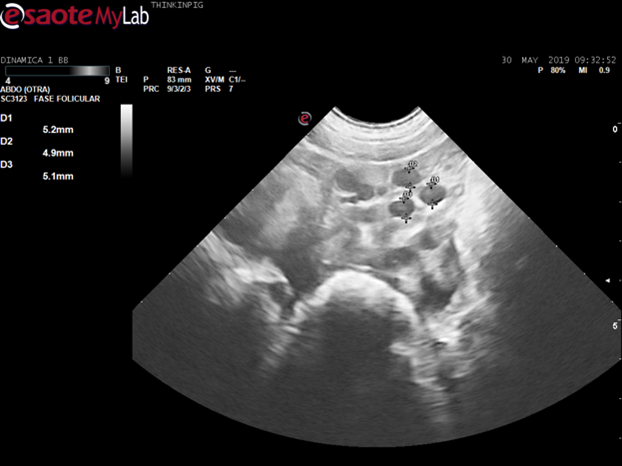

Una vez realizadas las ecografías en la zona de preparación de la nulípara, se procedió al diagnóstico ecográfico de las cerdas destetadas en la zona de cubrición, debido a que se reportaba una tasa del 12% de repeticiones en la granja. Para este caso, se realizó un estudio de dinámica folicular. Dicho estudio requiere ser realizado por un profesional en el tema y preferiblemente con equipos de mayor resolución. El procedimiento fue llevado a cabo por Antonio Vela y se empleó un ecógrafo Esaote MyLab Delta, con una sonda microconvexa de 8,5 Mhz.

Conociendo la dinámica folicular, se puede predecir el momento de ovulación. Folículos de 3-4mm ovularán en 40 horas, folículos de 5mm ovularán en 32-35 horas, folículos de 6-7 mm ovularán en 24 horas y la ovulación se llevará a cabo cuando el folículo mida entre 8- 9mm (Williams et al, 2017).

Folículos preovulatorios de 5,2mm (a 37 horas de ovulación). Imagen cedida por A.Vela